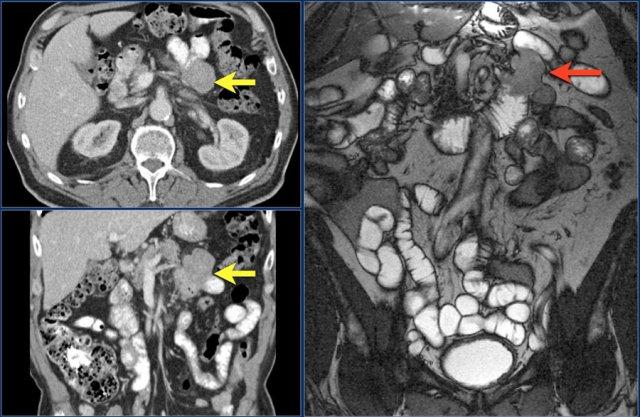

Hãy quan sát ảnh CT tái tạo mặt phẳng coronal.

Sau đó tiếp tục đọc.

Các dấu hiệu hình ảnh:

- Tổn thương hẹp lòng tá tràng do ung thư biểu mô tuyến (mũi tên vàng).

- Không thể phân tách khỏi tụy (mũi tên đỏ).

- Giãn tá tràng trước chỗ hẹp.

Các hình ảnh cho thấy một khối hình vòng ngắn gây tắc nghẽn ở hỗng tràng (mũi tên vàng) kèm hạch bạch huyết to (mũi tên đỏ).

Kết quả giải phẫu bệnh xác nhận là ung thư biểu mô tuyến.